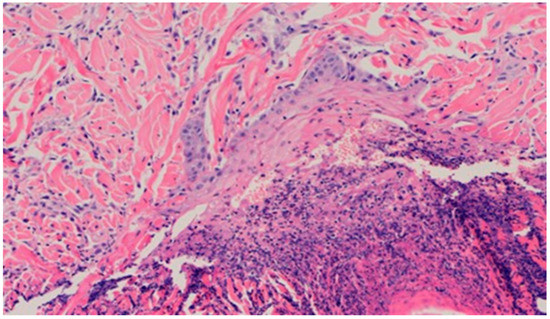

On day 15, the wound samples examined differed significantly, depending on the therapeutic agent used. The wound treated with the 1% propolis ointment was characterized by a consistently slight epidermization and moderate neovascularization, as was on day 10; however, the wound showed no foci of superficial necrosis. Additionally, the type of inflammatory infiltration changed into a lymphocytic-granulocytic one. The wound in the experimental group D2, treated with the 1% nanosilver ointment, and the wound in control group K, treated with sulfathiazole, continuously showed the progression of inflammation, from moderate to severe. On day 15, the wounds from the experimental group D2 and control group K were covered with large superficial necrosis.

The wound treated with the 1% nanosilver ointment showed high neovascularization, with no epidermization at the same time. The wound from group D3, treated with a mixture of 1% propolis and 1% nanosilver, showed a constant moderate inflammatory infiltration, however, with a change of type on day 15 to lymphocytic-granulocytic. Additionally, on day 15, the wound in the D3 experimental group was covered with a slight superficial necrosis with moderate neovascularization. The wound showed no signs of epidermization. The histopathological findings from day 15 are presented in Table 10 and Figure 18 and Figure 19.

Figure 18. Dermis with high-density granulocytic inflammatory infiltration (100×, H-E) in the sulfathiazole-treated wound on day 15.

Figure 19. Superficial necrosis. Major neovascularization (40×, H-E) in the wound treated with the 1% nanosilver ointment on day 15.